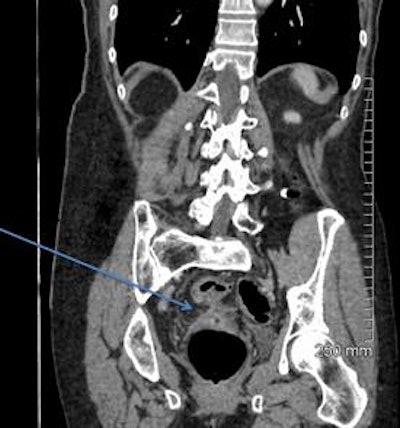

A 68-year-old woman with a fistula, categorized as C1D4E2, between the diverticular sigmoid and the vaginal vault. All images courtesy of Dr. John Hanson.

A 52-year-old man with a benign stricture, categorized as C4E1D4. The arrows highlight the smooth gradual transmural thickening within a diverticular laden sigmoid colon. Benign stricture was confirmed with surgical resection.